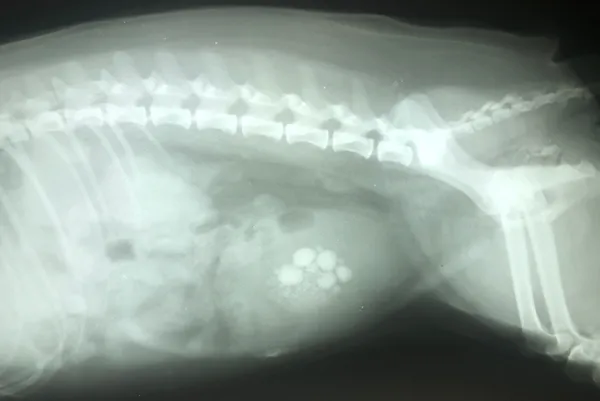

Most bladder stones are visible on X-rays or by an ultrasound exam of the bladder. Some types of bladder stones are radiolucent, meaning they cannot be seen on a normal X-ray, because their mineral makeup does not reflect X-ray beams. They can be detected by an ultrasound examination or with contrast X-rays, a specialized technique that uses dye or contrast material to outline the stones within the bladder.